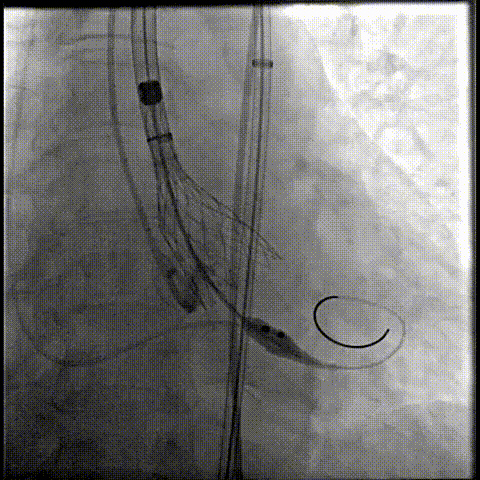

80%工作位评估

23球囊后扩

最终造影形态位置良好,轻微瓣周漏

术后压差降为0mmHg